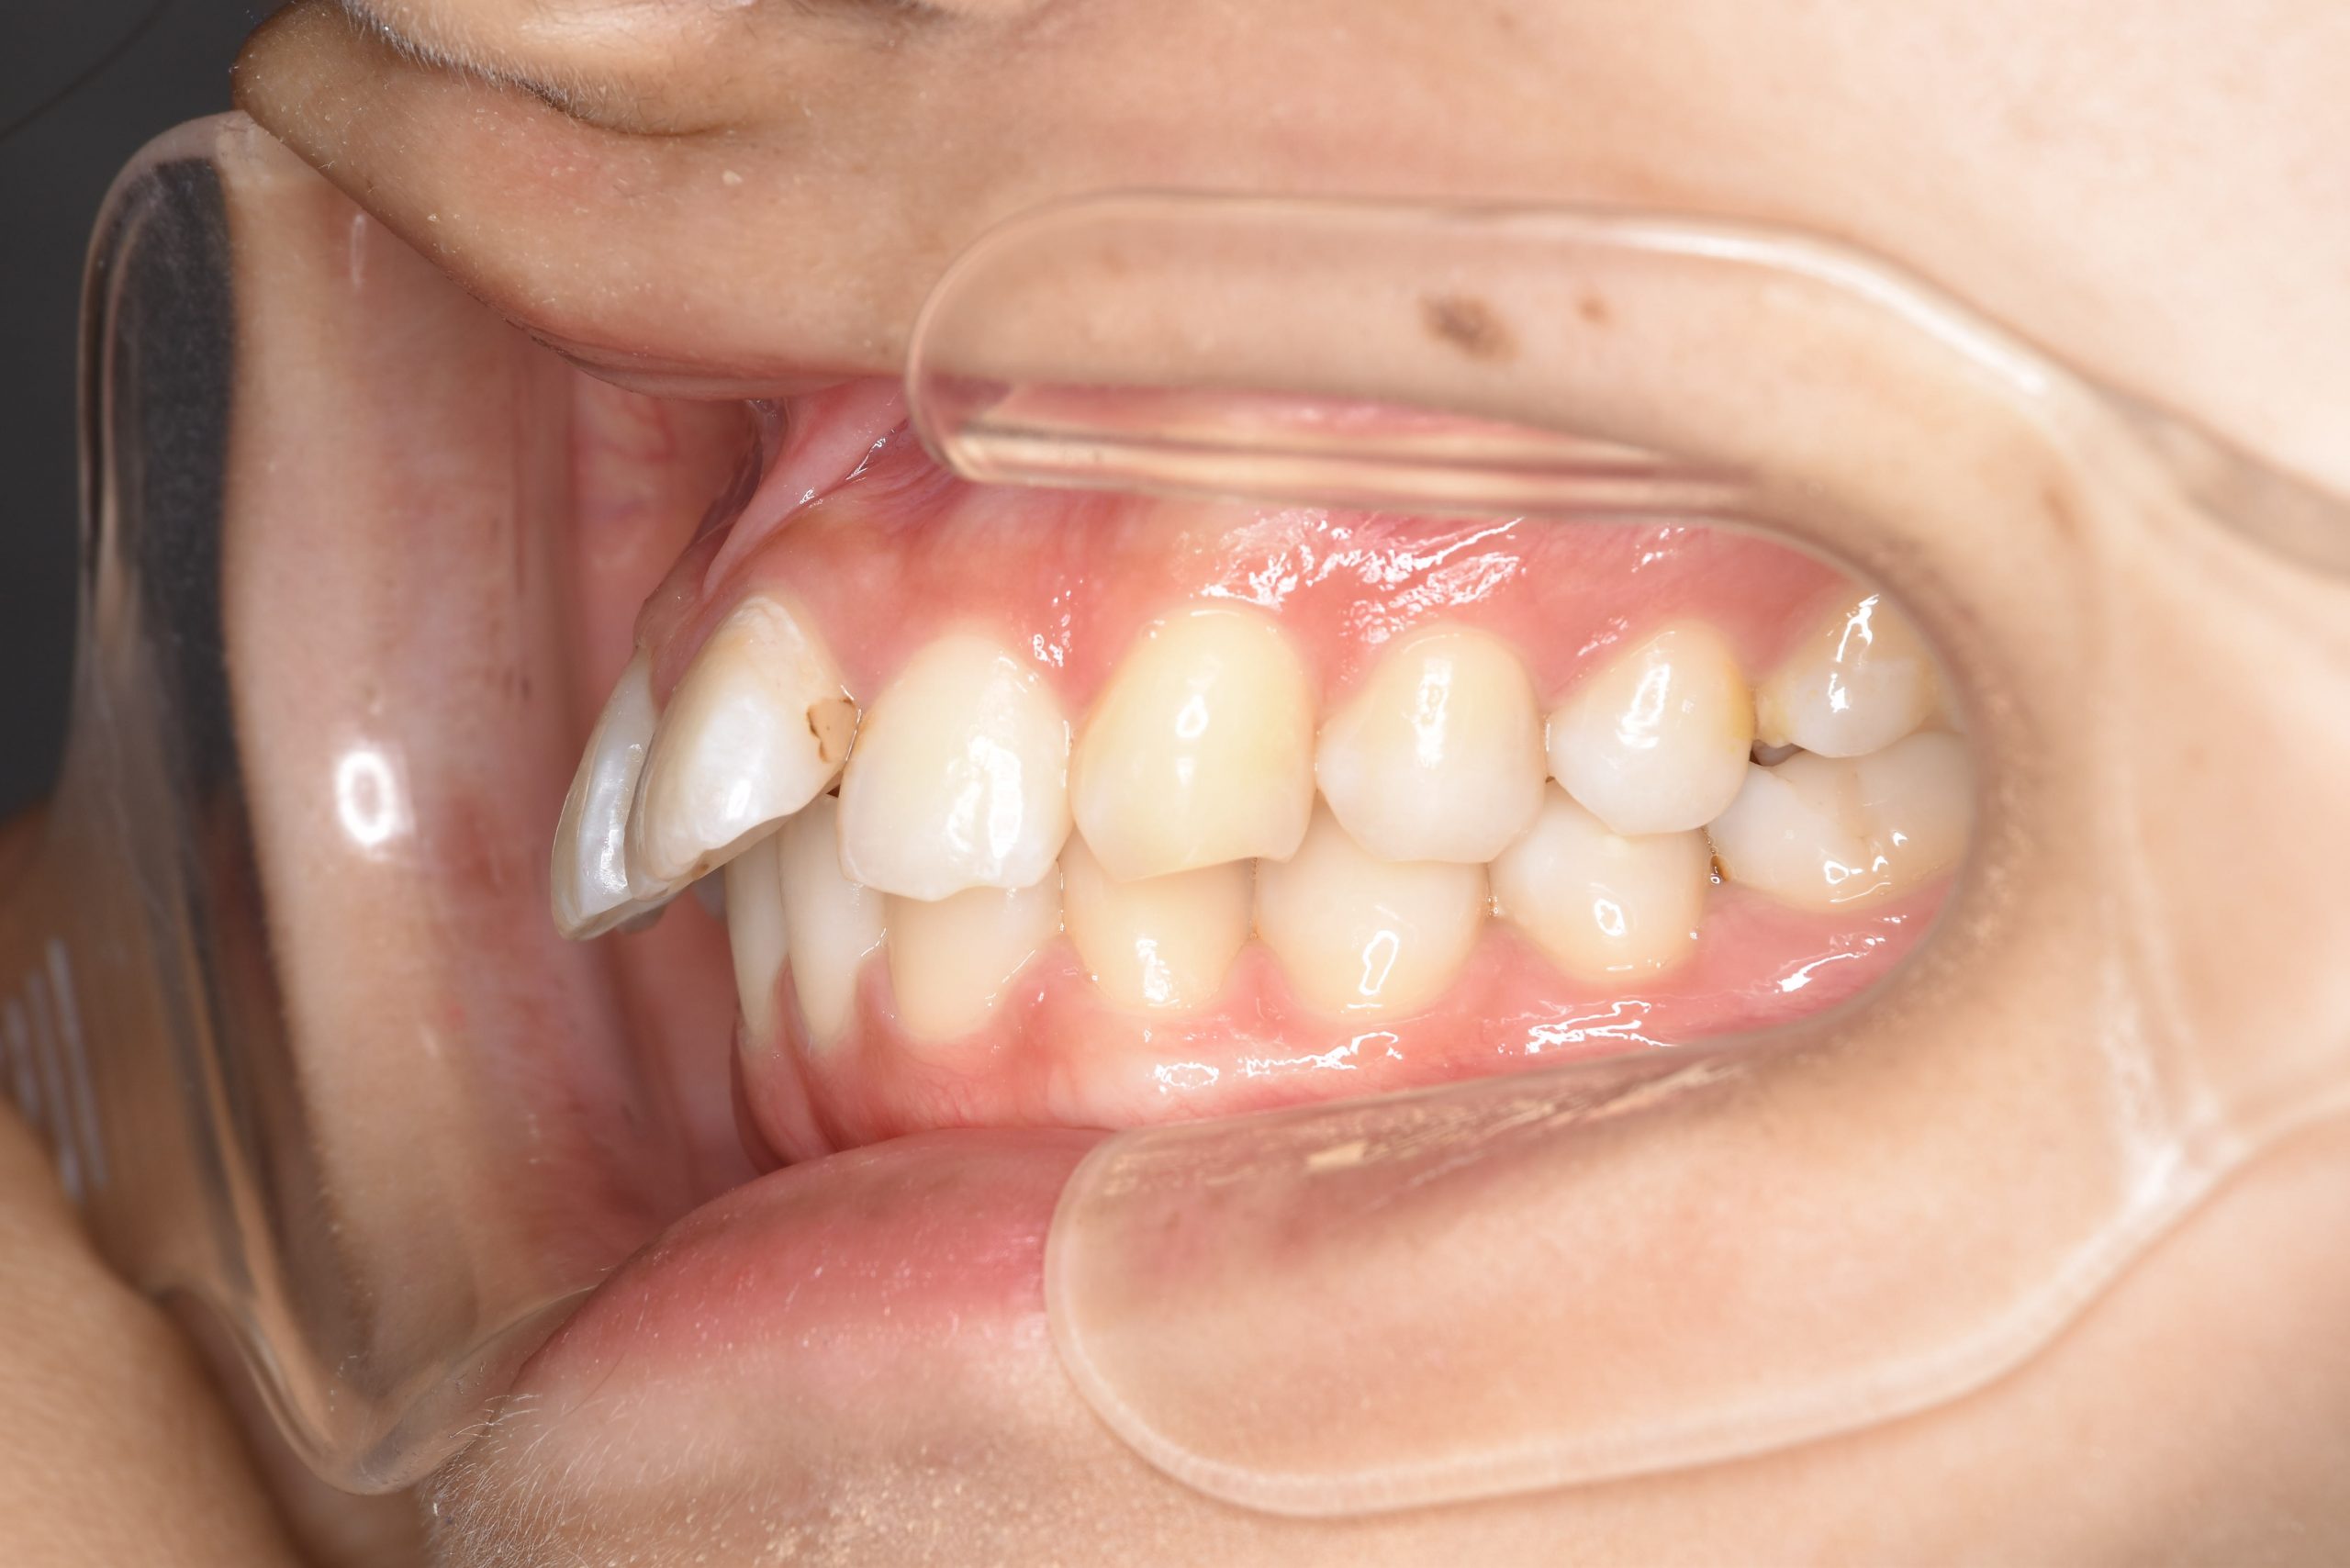

ビフォー

ワイヤー矯正治療|症例_009

主訴 出っ歯

施術内容 MSEと下顎リンガルアーチを用いて上下顎骨を拡大した。

その後マルチブラケット装置とミニインプラントを用いて非抜歯で歯牙を配列した。

下顎前歯が1本先天性欠損であったが、良好な咬合を獲得した。口元の突出感と鼻閉症状は改善された。